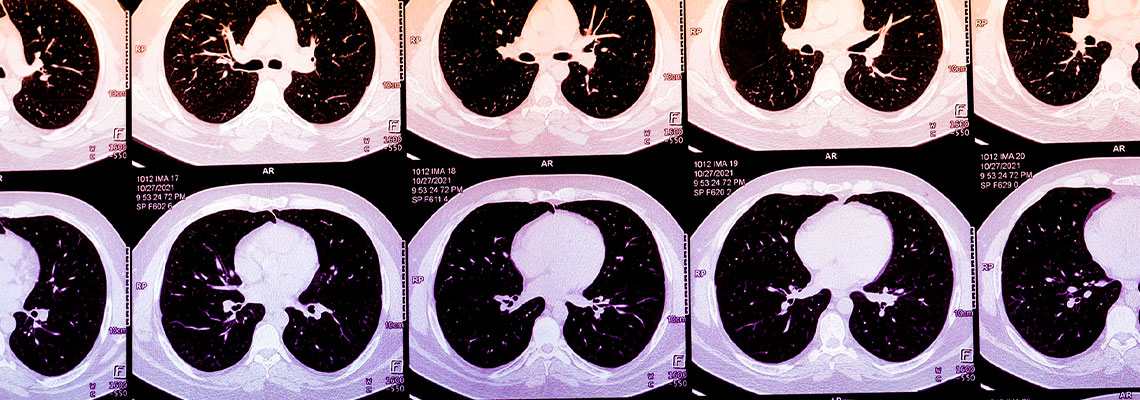

No ano passado, estima-se que 20 milhões de americanos tenham realizado tomografias computorizadas ao tórax, após um evento como um acidente de viação ou para rastreio de cancro do pulmão. Frequentemente, estas imagens revelam evidências de cálcio nas artérias coronárias (CAC), um marcador de risco de ataque cardíaco, que permanece escondido ou não é mencionado num relatório de radiologia focado em descartar lesões ósseas, traumas internos com risco de vida ou cancro.

O cálcio nas artérias coronárias pode muitas vezes ser visto em tomografias ao tórax, e a sua concentração pode ser descrita de forma subjetiva. Normalmente, quantificar o escore de CAC de uma pessoa implica obter uma tomografia computorizada específica do coração. No entanto, algoritmos que calculam escores de CAC a partir de tomografias de rotina ao tórax poderiam ampliar de forma massiva o acesso a essa métrica. Na prática, estes algoritmos poderiam ser usados para alertar pacientes e os respetivos médicos sobre escores anormalmente elevados, incentivando-os a procurar cuidados adicionais. Hoje, a presença de startups que oferecem escores de CAC derivados de IA ainda não é grande, mas está a crescer rapidamente. À medida que o uso aumenta, estes algoritmos podem identificar pacientes de alto risco que tradicionalmente passam despercebidos ou que estão na margem do sistema de cuidados.